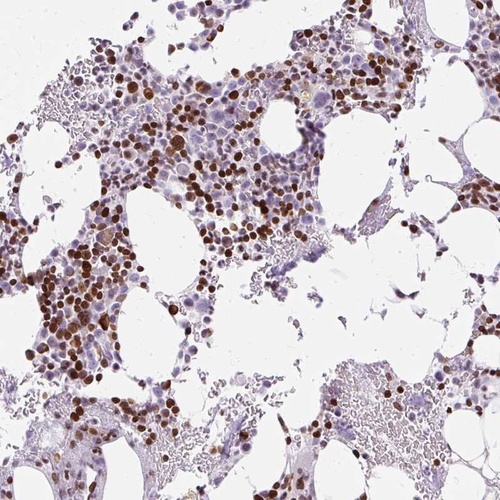

Immunohistochemical staining of human bone marrow shows strong nuclear positivity in hematopoietic cells.